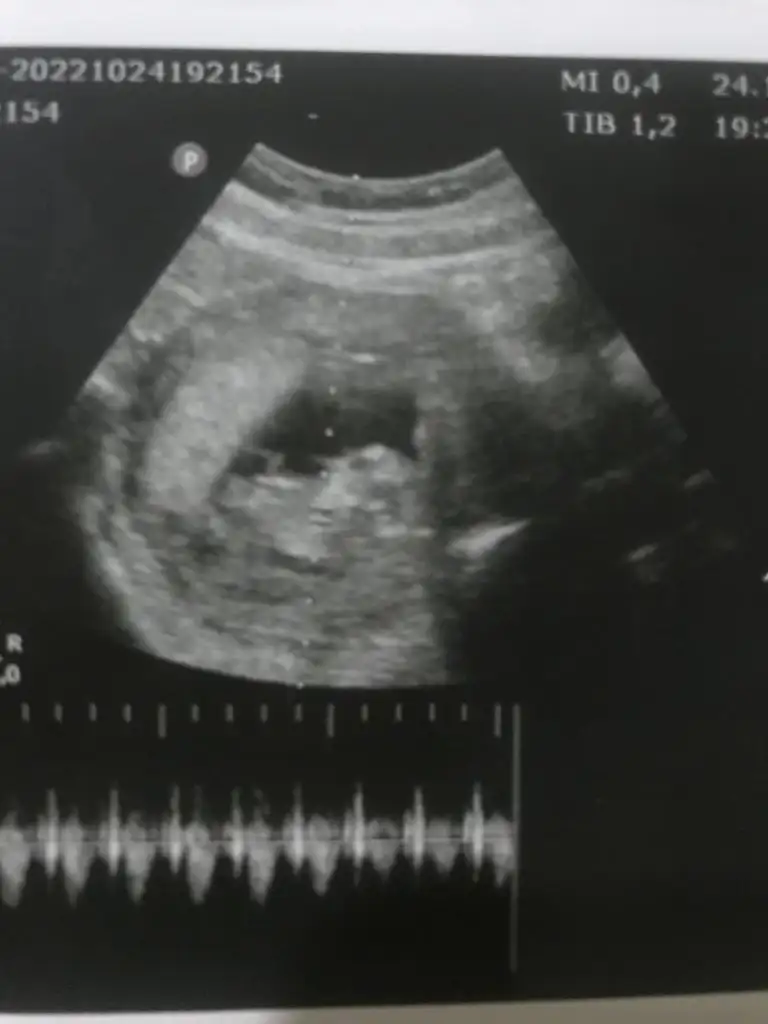

Buda usg lerimSelam Kızlarbir çok kişi gruplardan beni bilir. Yine yetiştim imdatlara

Geçen birkaç video izlemiştim. Genital kısımda 3 tane ince beyaz çizgi olunca kız diye anlatıyordu doktor. Bayağı örnek görmüştüm. Siiznki de öyle duruyor ama tabiki. Bu sadece bir tahmin allah gönlünğzden geçeni nasip etsin inşallahnerden anladınız acaba :)